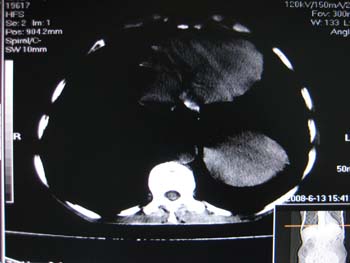

女,65岁,左上腹痛。

肝脏占位  脾脏及胰腺病变   请提供病史

肝脾胃左肾胰都显示不正常啊

病史不详,肝、脾、胰都有占位,谁是原发?

淋巴瘤及肝癌(转移瘤?)可不可以不用一元论解释呢。

肝脏 脾脏 胰腺都有病变.

胰腺癌伴脾脏侵犯并肝内转移可能性大  建议增强扫描  否则没有确凿的依据

考虑姨尾癌,腹膜后转移\\肝转移

没有病史,没有强化,那就只有猜了,我看病灶很像肝、脾及腹腔多发脓肿,这只是我的意见,

图像欠清,病灶与胃脾胰肾上腺关系显示欠清,建议增强,肝脏考虑转移瘤.

多脏器占位,腹膜后淋巴结增大,淋巴瘤?建议增强扫描